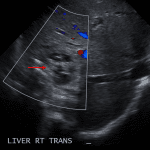

- Complex lesion in the right hepatic lobe measuring 5.2 x 4.5 x 4.2 cm with a hyperechoic rim, multiple rounded internal hypoechoic areas, and no internal Doppler flow

- Small volume perihepatic free fluid

- Borderline dilation of the common bile duct, measuring up to 6-7 mm, without intrahepatic biliary duct dilation

Hydatid cyst

Complex lesion in the right hepatic lobe measuring 5.2 x 4.5 x 4.2 cm with multiple internal cystic areas and no internal vascularity. Differential considerations include a multilocular pyogenic abscess, hydatid cyst, and necrotic/cystic neoplasm.

Mild extrahepatic biliary duct dilation without obstructing mass or stone identified. MRCP or ERCP could provide further evaluation.

Small volume perihepatic free fluid, likely reactive.